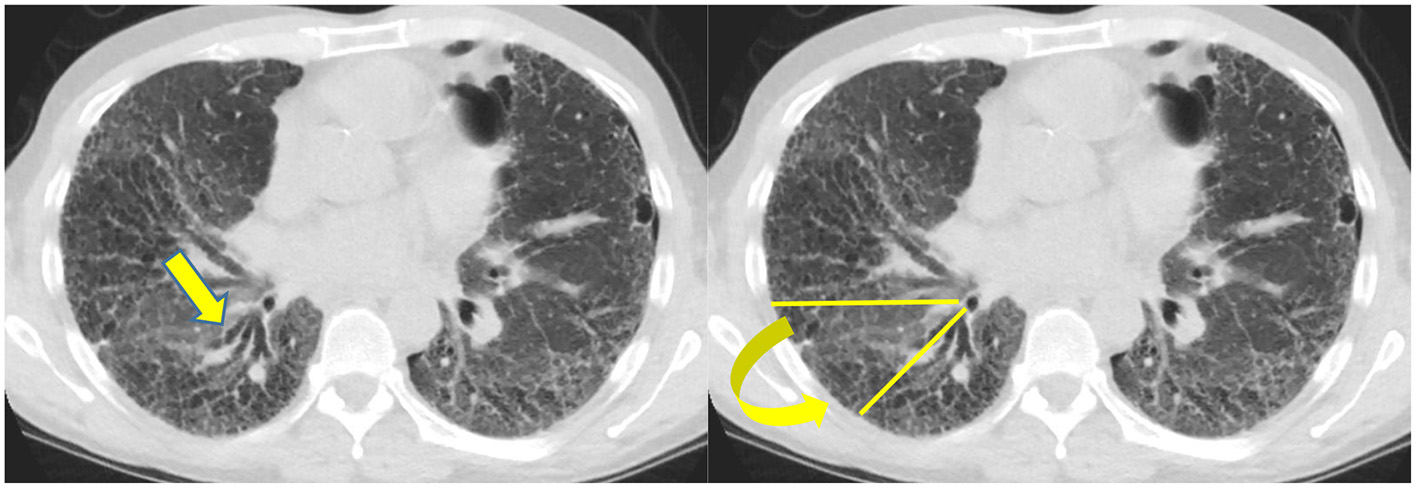

Biomarkers are medical signs which can be measured and used to diagnose disease (27). Radiology can function as a biomarker. In fibrotic NSIP, the lower lobe predominant scarring diminishes the volume of the inferior lung and displaces the major fissures posteriorly, more so than UIP, which is also a lower lobe predominant fibrotic disease. An increase in the amount of volume loss for this disease can be used in part to identify a progressive phenotype (28) (Figure 4).

Figure 4

Typically the right lower lobe anterior bronchus (yellow arrow) follows a horizontal course but in this patient it is displaced posteriorly by volume loss and fibrosis. The displacement of the bronchus can be followed to document disease progression.